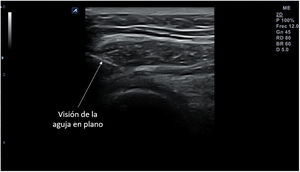

La punción se puede hacer en el eje largo de la sonda, denominada también «en plano» (fig. 14), con la aguja entre 30 y 45° de inclinación respecto a la superficie, lo que permite visualizarla en todo su trayecto, y lo hace muy recomendable cuando haya riesgo de lesionar estructuras cercanas. La aguja aparecerá en la pantalla como una línea hiperecogénica brillante con artefacto de reverberación (al ser un objeto metálico, se dibujarán líneas paralelas hiperecogénicas por debajo de la misma por un efecto espejo). Para poder visualizar correctamente todo el trayecto de la aguja, esta debe orientarse en el mismo plano de corte de la sonda.

En otros casos interesará realizar un abordaje en el eje corto de la sonda, denominado «fuera de plano»(fig. 15) introduciendo la aguja perpendicular a la sonda, en su parte media, de modo que en la pantalla será visible únicamente la punta. Esta técnica no permite seguir el trayecto completo de la aguja en un solo corte, pero ofrece una imagen precisa de su punta. El uso de una u otra técnica dependerá de las preferencias del profesional que realice la técnica, del tipo de punción y de las condiciones anatómicas de la zona.